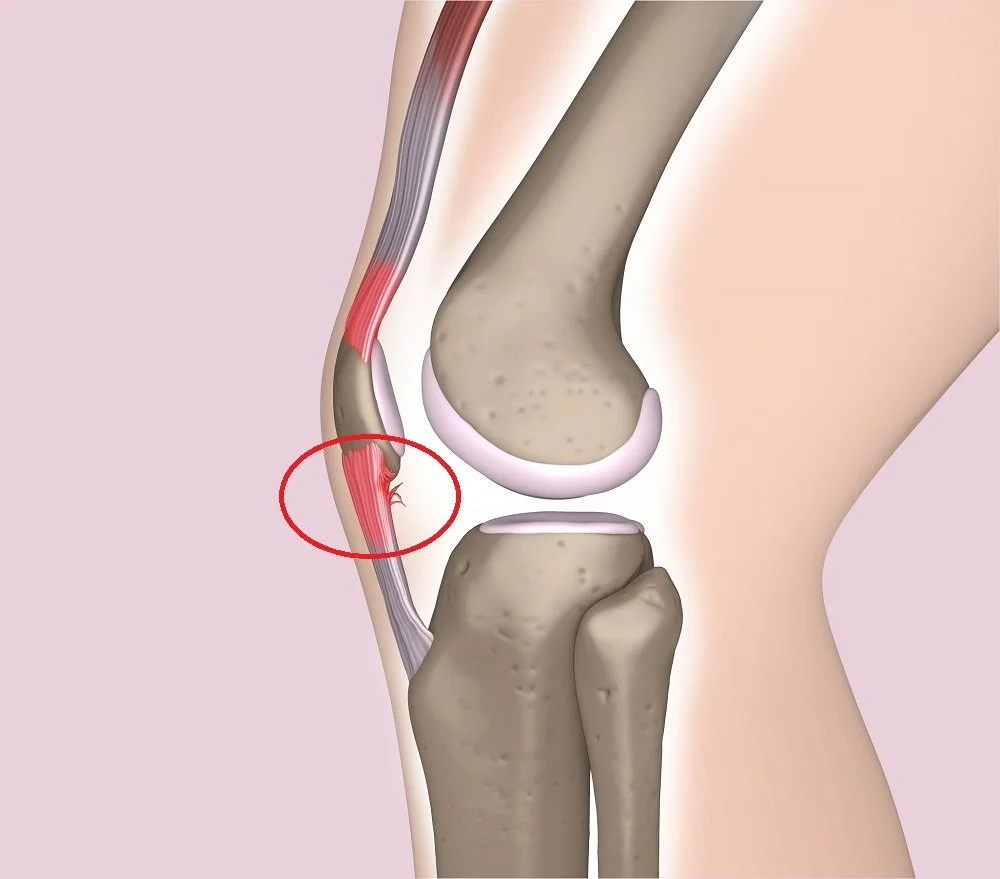

Jumper's Knee (Patellar Tendinopathy)

Jumpers Knee, or Patellar Tendinopathy, is a complex knee injury that Physiotherapists treat regularly. Read more about its common symptoms, causes, and how best to fix this injury.